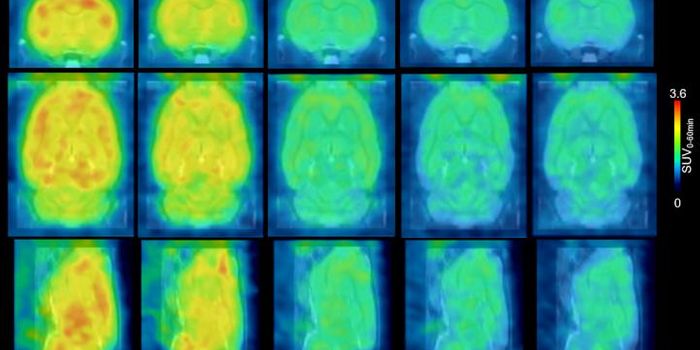

SEP 19, 2019NeuroscienceResearchers from the University of California have found a low-cost, non-invasive method to aid in diagnosing Alzheimer& ...

FEB 01, 2022Clinical & Molecular DXNeuroscientists have found a link between hotspots of brain overactivity and specific symptoms of schizophreni ...